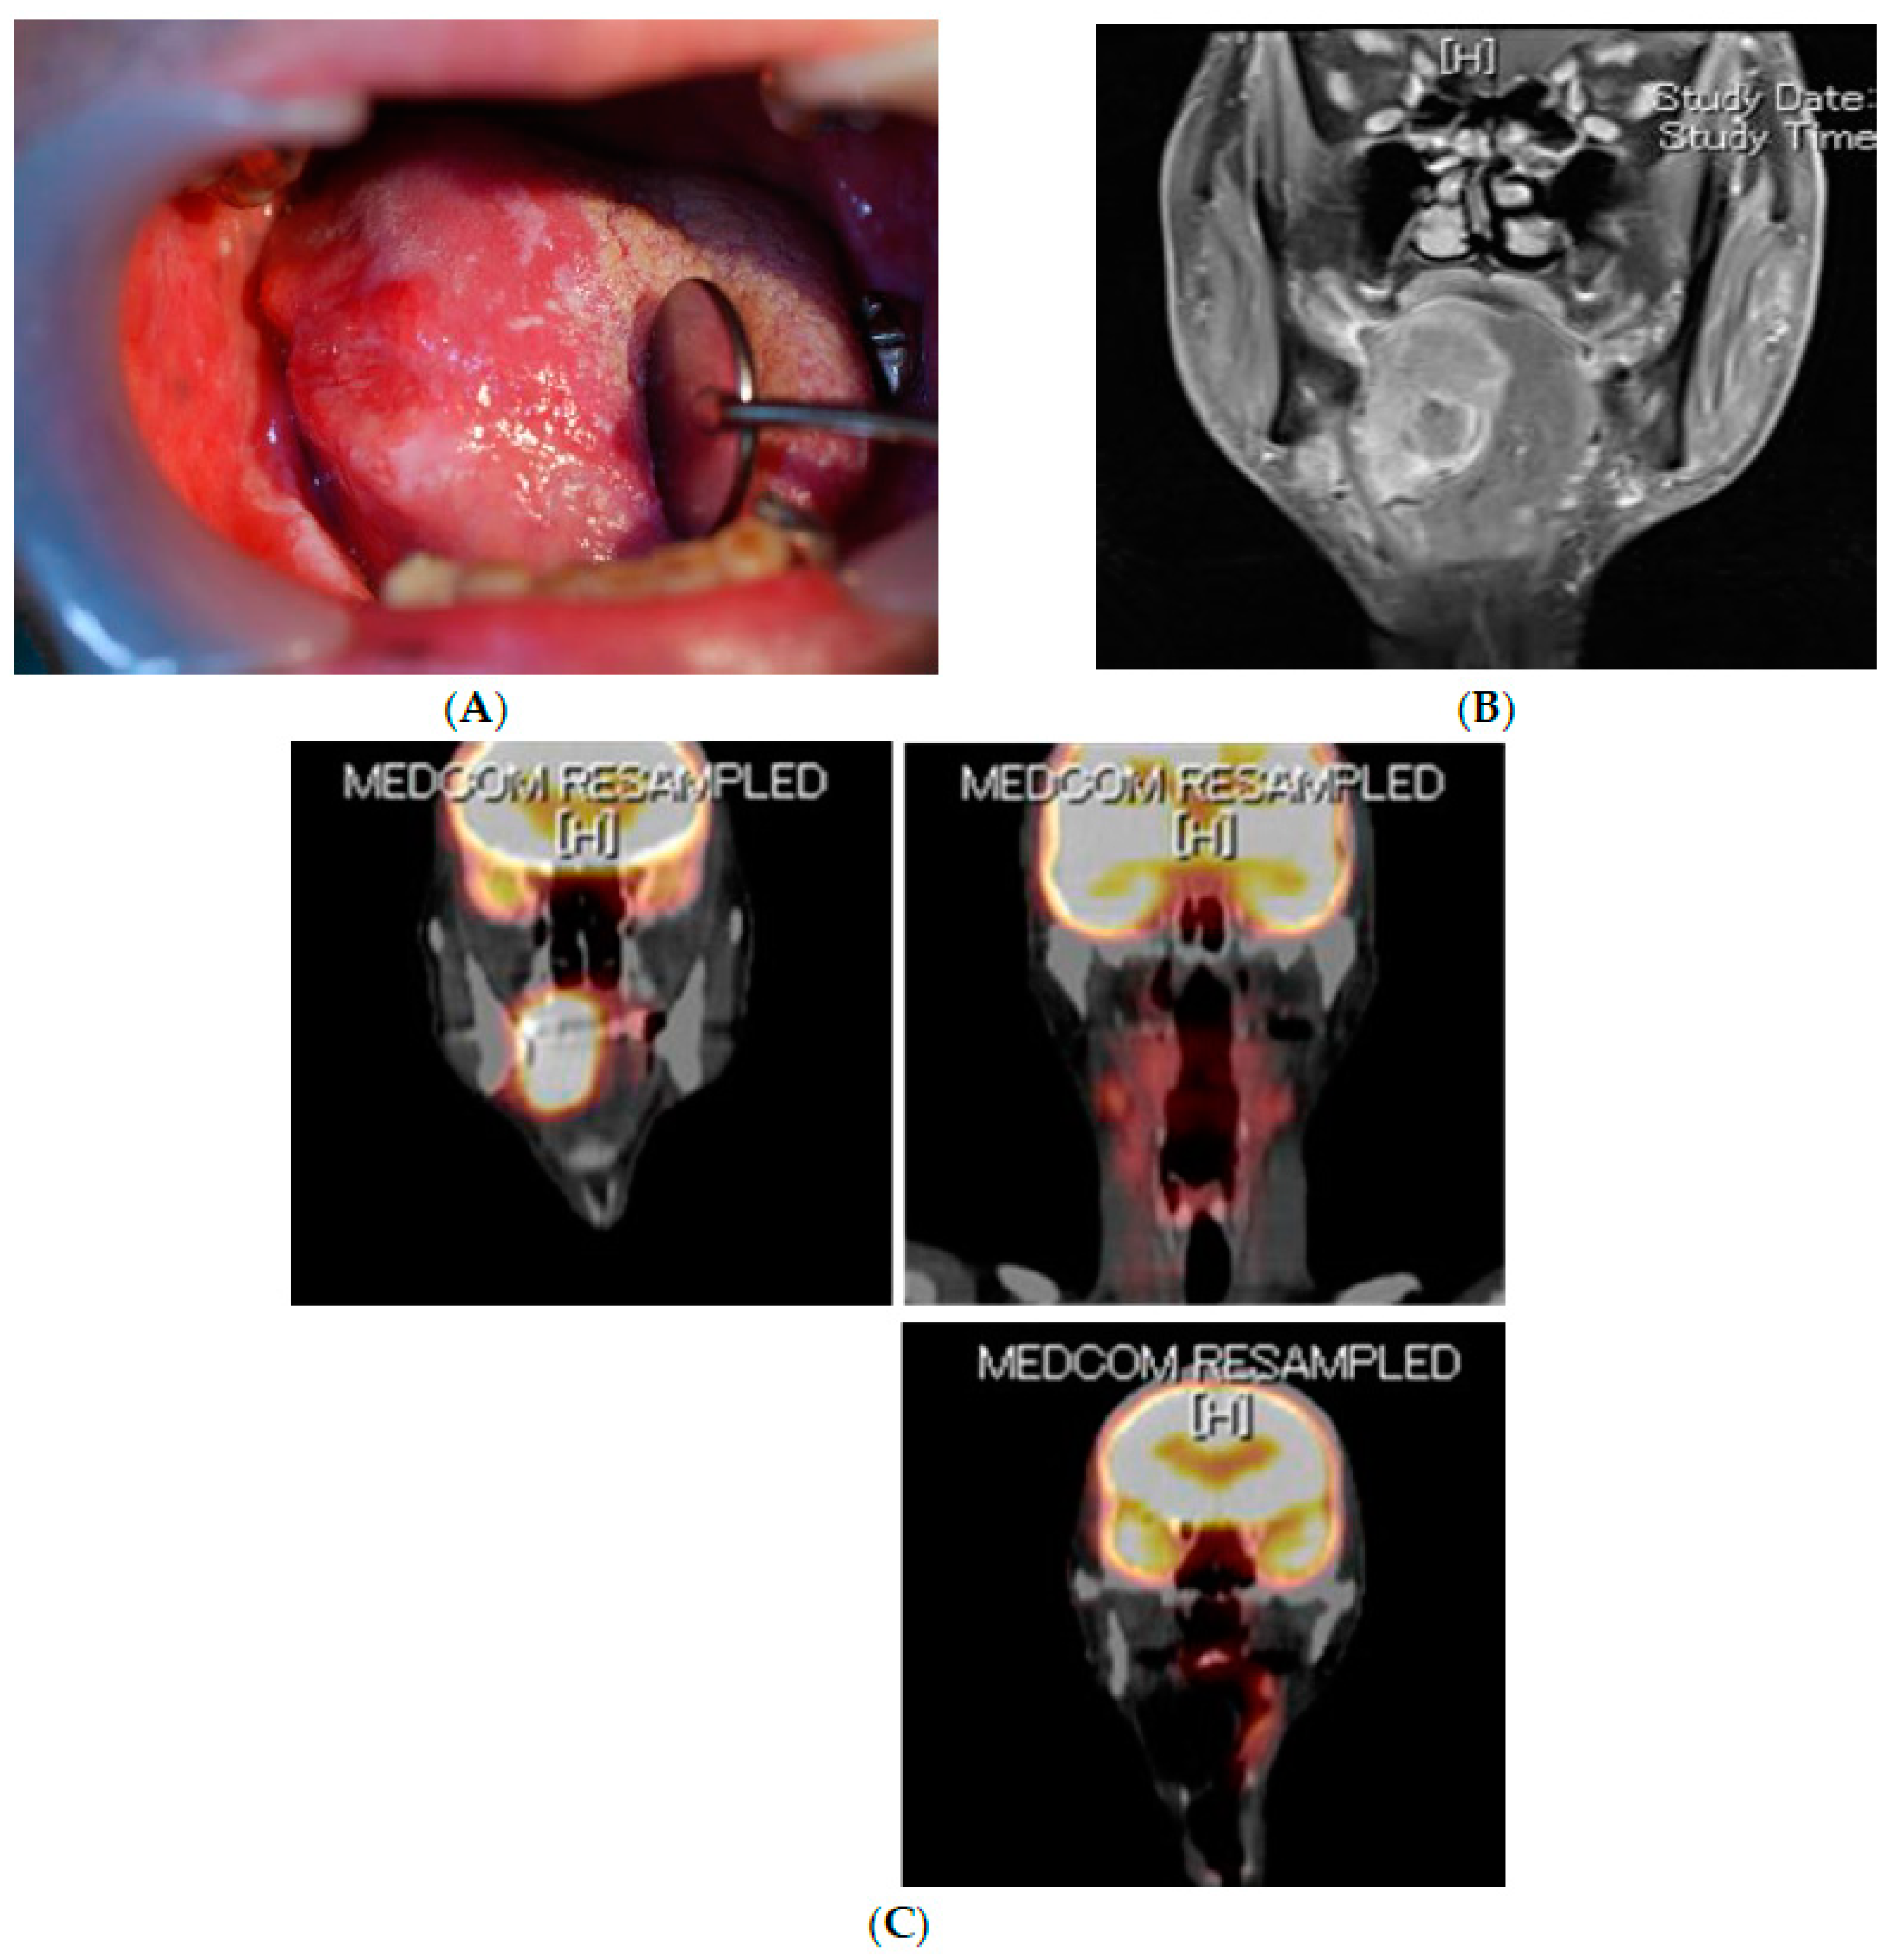

- Hasegawa, T.; Nakashiro, K.-I.; Fukumoto, C.; Hyodo, T.; Sawatani, Y.; Shimura, M.; Kamimura, R.; Kuribayashi, N.; Fujita, A.; Uchida, D.; et al. Oral squamous cell carcinoma may originate from bone marrow-derived stem cells. Oncol. Lett. 2021, 21, 1. [Google Scholar] [CrossRef]